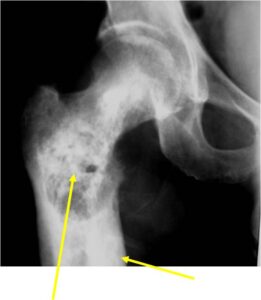

Sites:

- Most common in pelvis, proximal femur, proximal humerus, distal femur, ribs

Radiology emulates pathology: Biphasic Tumor

- One region low grade chondrosarcoma

- Second more aggressive area with bone destruction, lysis of calcification, soft tissue mass

- Cortical permeation and a soft tissue mass in 70% of cases

Ill-defined, lytic intraosseous lesion

Characteristically abrupt transition between chondroid tumor and dedifferentiated, lytic component

Bone may be expanded and adjacent cortex thickened